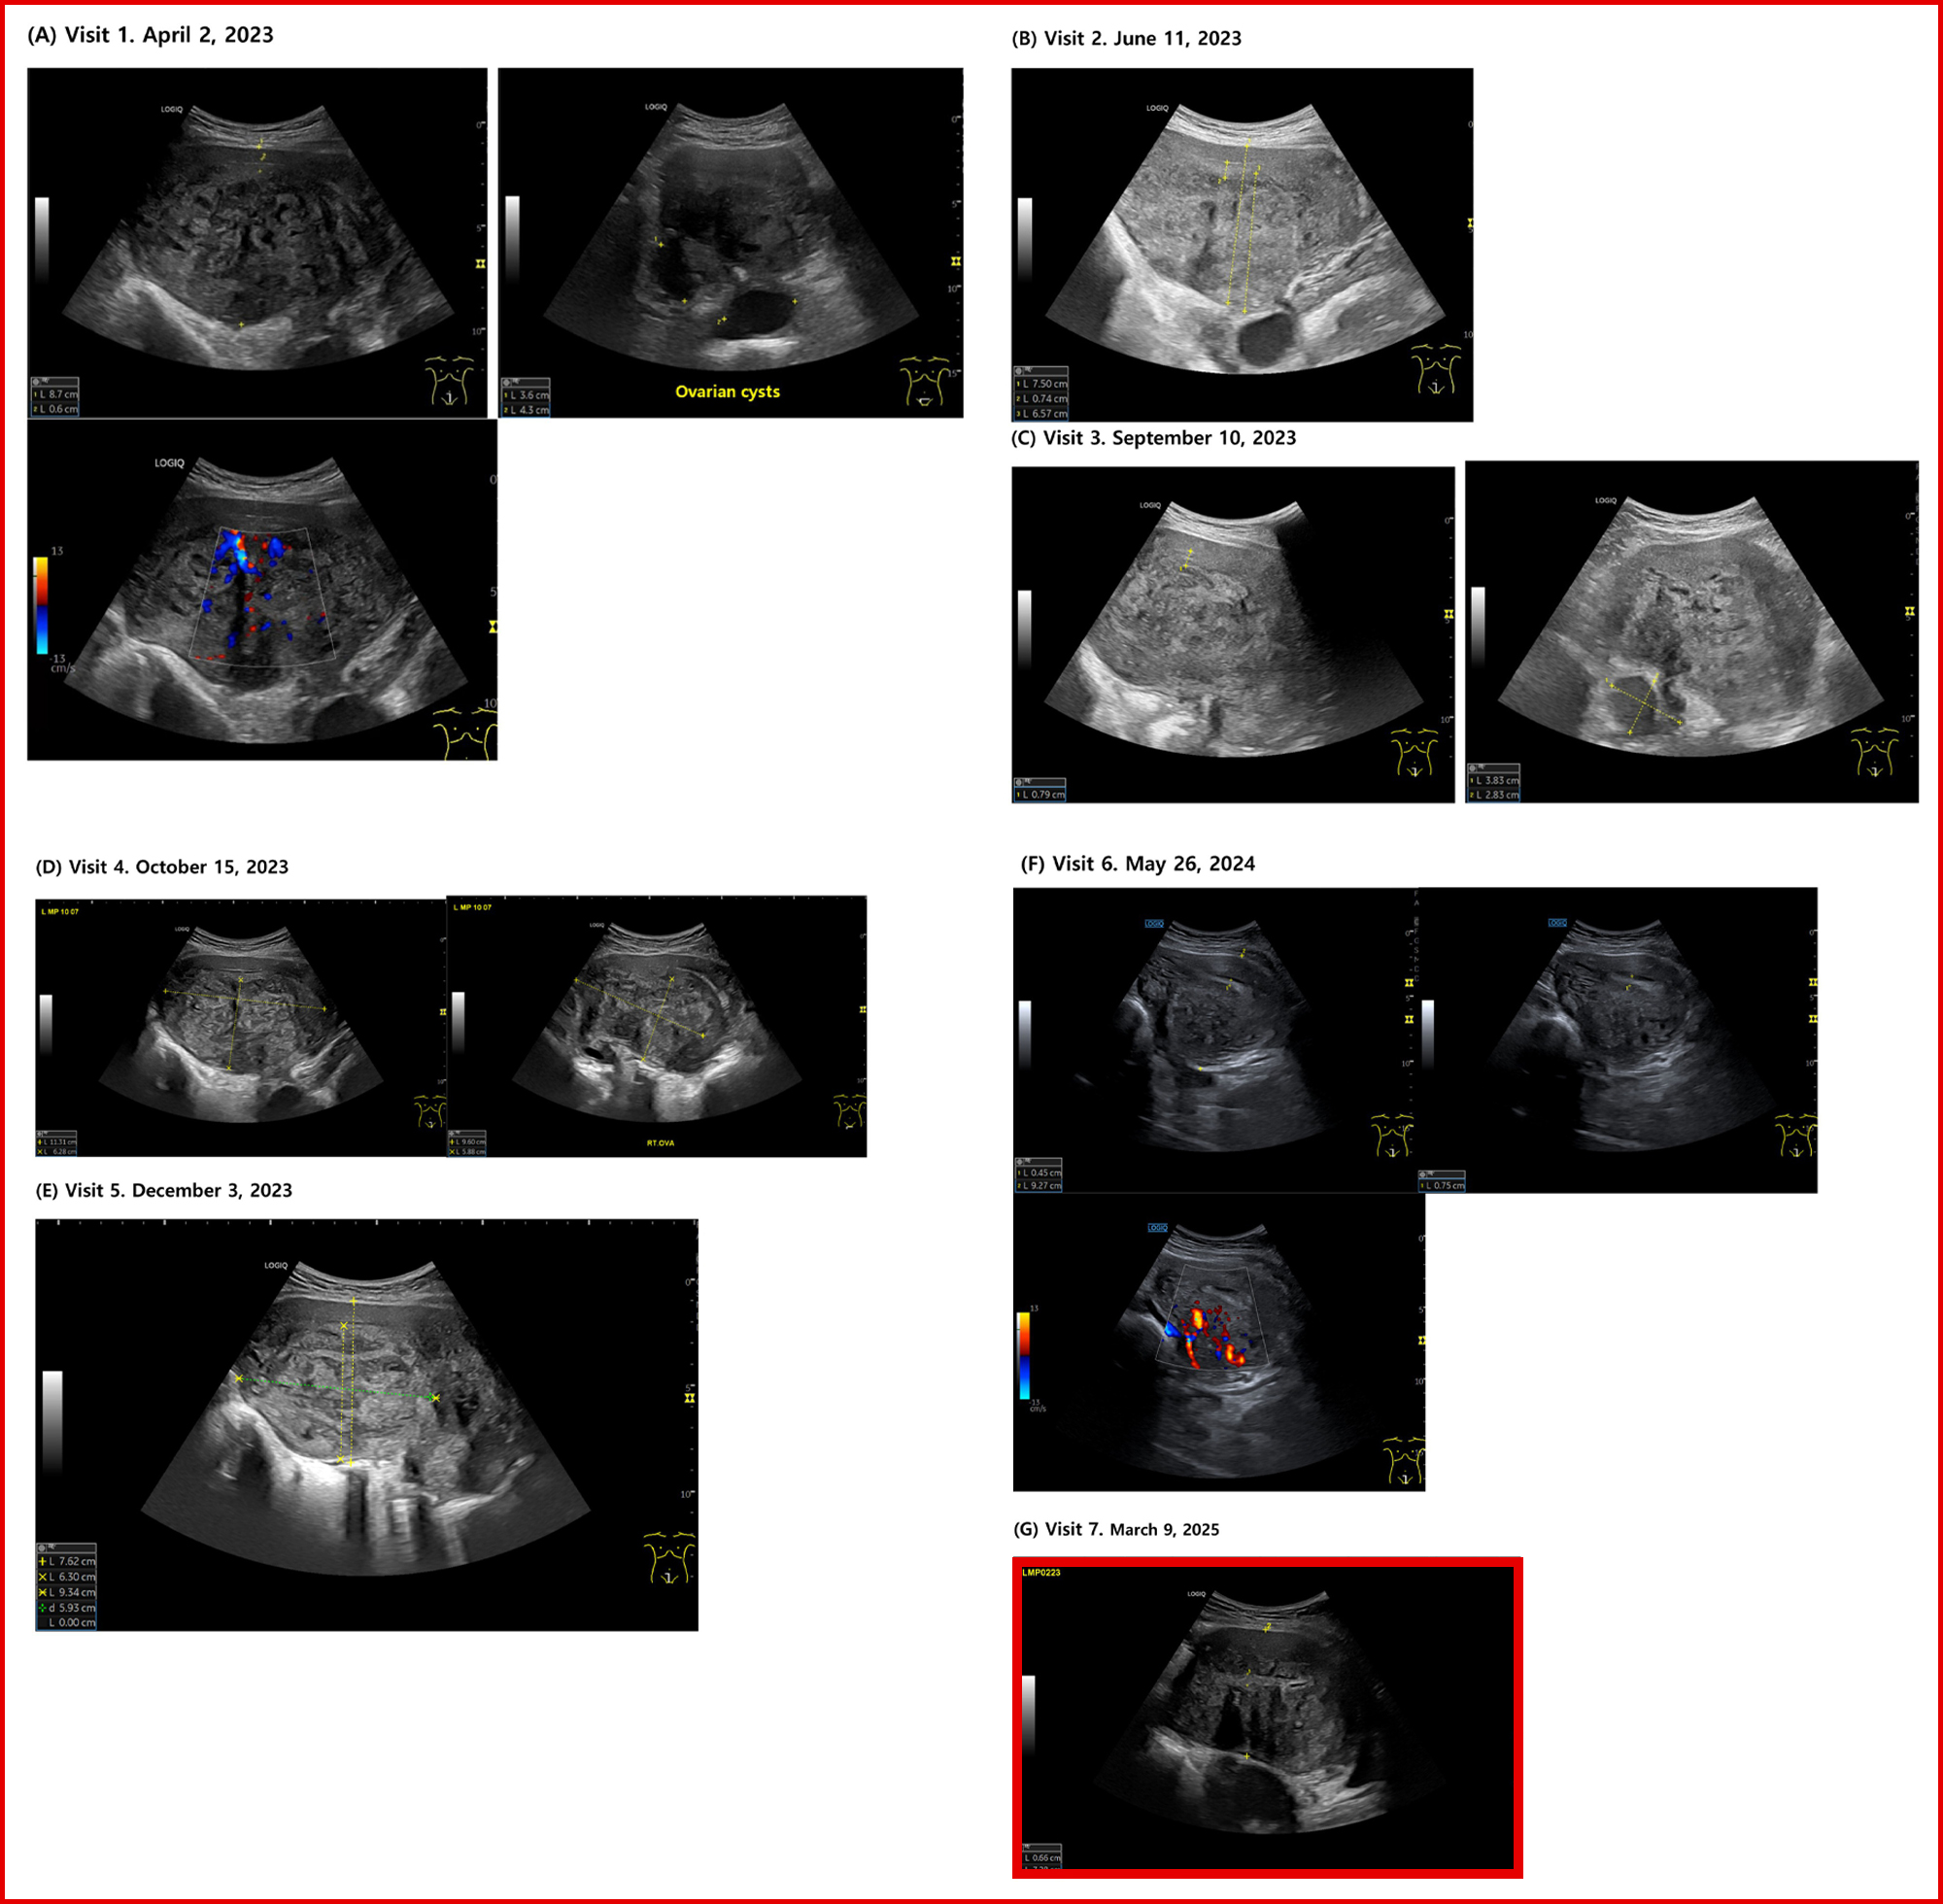

이에 환자는 보중익기탕 가감방 투여 후 6주 만에 생리통(NRS)은 7~8에서 4~5로 완화됐고, 초음파상 자궁 AP 길이는 8.7cm→7.5cm로 감소한 데 이어 5개월 후 혈액검사에서 헤모글로빈 수치가 10.4로 회복됐으며, 자궁근층의 정상화 소견이 확인됐다.

또한 8개월 시점에는 월경 주기가 28~29일로 정상화되고, PBAC가 400에서 55로 감소했으며, 생리통 NRS 1~2로 진통제 복용이 불필요해졌다. 초음파에서는 고에코 섬, 근층 낭종 등 MUSA 2022 지표 다수가 개선된 것으로 확인됐다.

1년 치료 종료 시점에 삶의 질 지수(EQ-5D-5L)는 0.288에서 0.877로 상승했고, 자궁내막–근층 접합부(Junctional zone)의 규칙성이 회복된 상태에서 7.28cm 크기로 안정 유지됐다.

초음파.jpg

▲사진을 클릭하시면 자세히 보실 수 있습니다.